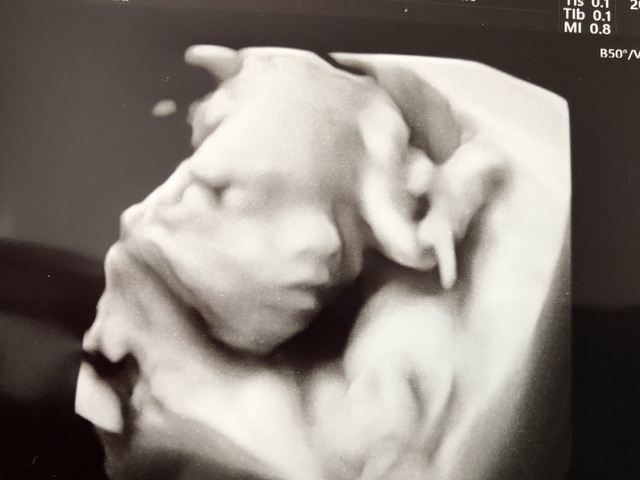

20週0日(20w0d・女の子)|もこまろa さん(32歳)

エコー写真撮影時のエピソード:

初めてエコーで赤ちゃんのかおが見れたときはとても感動したが、想像とあまりにも違う感じで、先生も「ちょっとホラーだね(笑)」と。

私も「本当、ホラーですね(笑)」と。

でもちゃんと目や鼻口の形があり、人間らしくなっていて安心してのを覚えています。